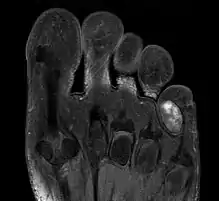

Chondroma of the soft parts located in the little toe.

Extraskeletal chondroma is a cutaneous condition, a rare benign tumor of mature cartilage.[1]